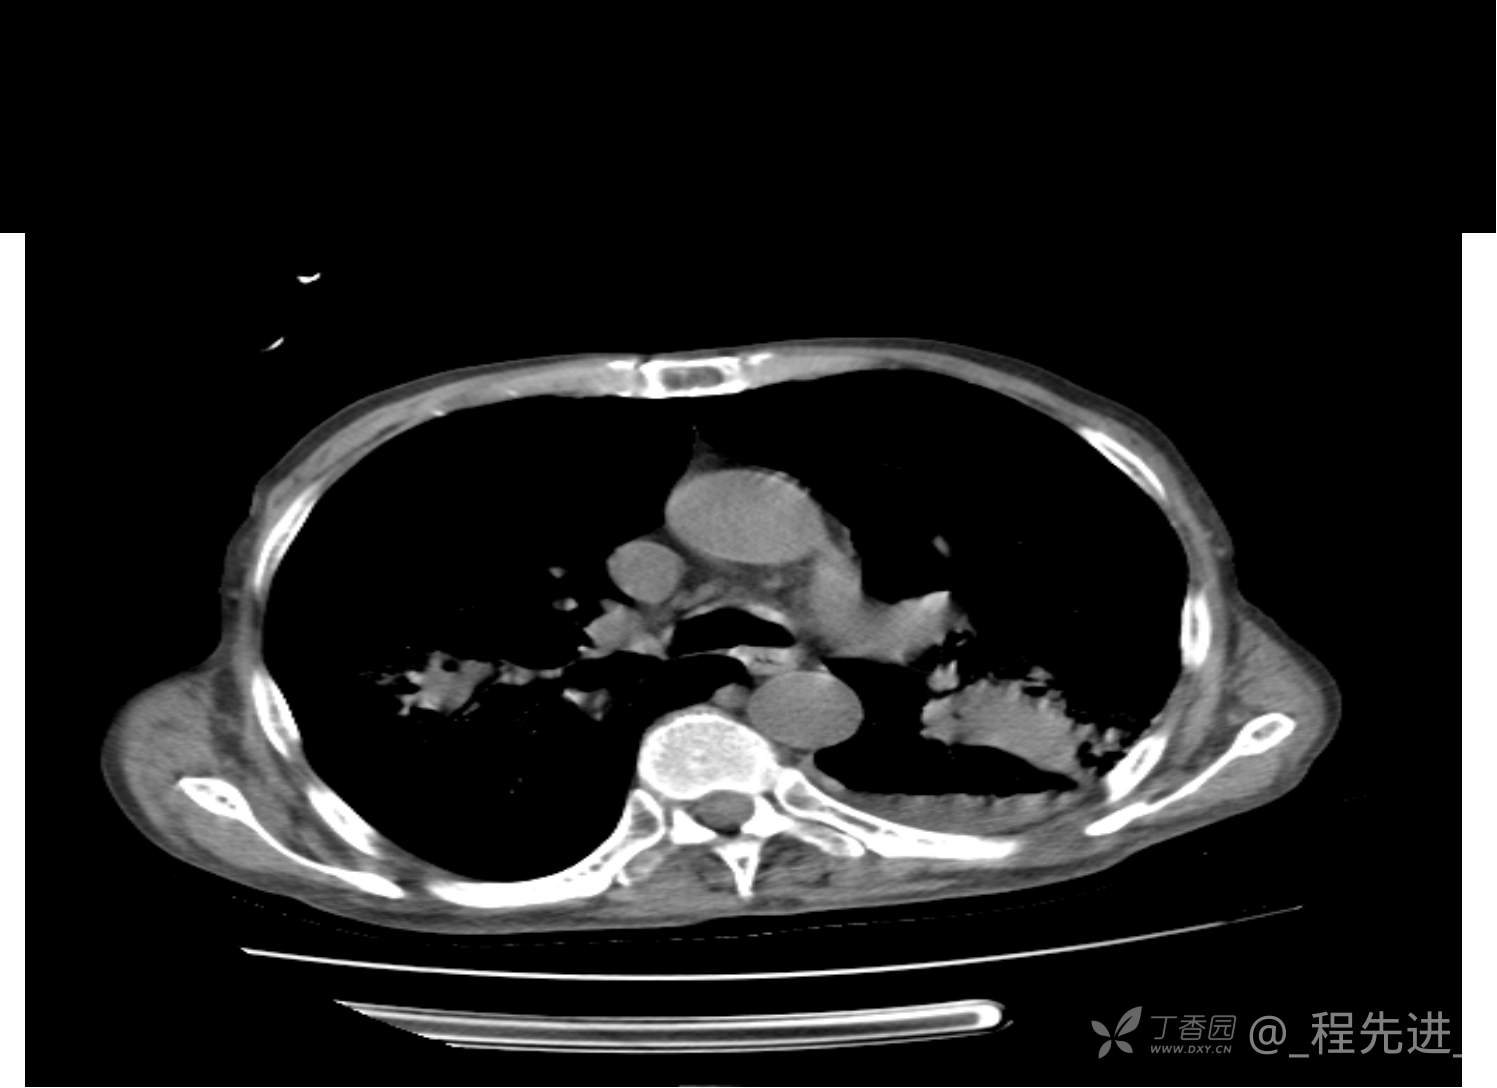

患者性别:男

患者年龄:81岁

简要病史:反复咳嗽、咳痰20余年,加重1周。两肺呼吸音低,可闻及散在干湿啰音。